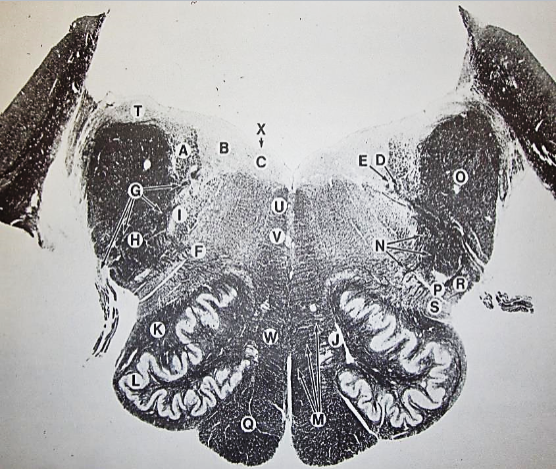

A

Fasciculus gracilis

B

gracile nucleus

C

fasciculus cuneatus

D

cuneate nucleus

E

spinal trigeminal tract

F+G collectively

spinal trigeminal nucleus

H

accessory nucleus

I

pyramidal decussation

J

rubrospinal tract

K

posterior spinocerebellar tract

L

anterior spinocerebellar tract

M

lateral spinothalamic tract

N

anterior spinothalamic tract

O

lateral vestibulospinal tract

P

medial longitudinal fasciculus

Q

tectospinal tract

A

Lateral Cuneate nucleus

B

dorsal external arcuate fibers

C + D collectively

vestibular nuclei

C + D collectively

vestibular nuclei

E

dorsal motor nucleus of vagus nerve

F

solitary fasciculus

G

solitary nucleus

H

nucleus ambiguous

I

fascicles of glossopharyngeal nerve

J

hypoglossal nucleus

K

fascicles of hypoglossal nerve

L

dorsal longitudinal fasciculus

M

central tegmental tract

N

inferior olivary nucleus

R

inferior cerebellar peduncle

S

spinal trigeminal tract

T

spinal trigeminal nucleus

U

ventral trigeminothalamic tract

V

pyramidal (corticospinal) tract

W

rubrospinal tract

X

anterior spinocerebellar tract

Y

spinal lemniscus

Z

medial longitudinal fasciculus

a

tectospinal tract

b

medial lemniscus

c

vagus nerve

d

inferior salivatory nucleus